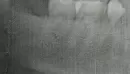

Врач положил лекарство под соседний зуб при удалении зуба мудрости (я об этом не знал). Сказал, придешь ко мне на полную чистку через 2 недели. Я не пришёл. Спустя время решил сделать рентген лунки, так как после удаления мне стало плохо и самочувствие не нормализовалось.

Зачем врач во время удаления зуба мудрости, под соседний зуб подложил шарик с девитализирующей пастой? Что делать?

Прикрепленые фото

В случае пульпита врач закрывает под временной пломбой девитализирующую пасту. Без клинического осмотра и оценки рентгеновского снимка, сделанного до лечения, судить невозможно. В любом случае вам стоит обратиться к стоматологу-терапевту для ревизии корневых каналов.